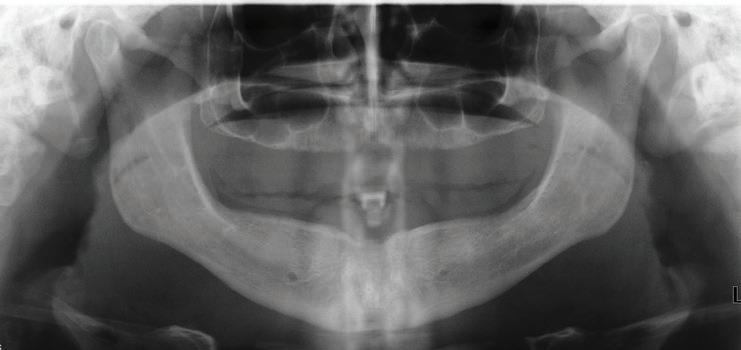

This patient is a 34-year-old male. He works as a dental assistant. His chief concern was, “I have temporary dentures that are six years old. They are discolored and do not fit well. I cannot eat with them.”

The patient was initially injured while playing college baseball when he was hit in the mouth with a baseball. As a result of this injury, the patient lost all of his teeth. This event was six years ago.

Medical History: The patient suffers from anxiety and depression. He is a tobacco smoker, and has smoked half a pack a day for 10 years.

Rx. History: Xanax, Effexor

Implants were placed in areas of nos. 22 and 27. Implant no. 22 was Nobel Replace RP 4.3x11.5 torqued to 42.1 N/cm; implant no. 27 was Nobel Replace RP 4.3x11.5 torqued to 45.0 N/cm. Due to the patient wearing dentures, cover screws were placed and horizontal mattress sutures were placed. (The ends were clipped after the photos.) The patient was seen two days after and was healing well He was very happy with his treatment.